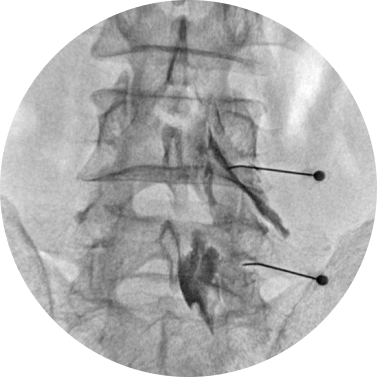

구로나르샤정형외과 신경차단술은 최신형 저방사선량의 CT를 이용한 정밀 진단으로 시작해 고출력 HLF 모드의 C-arm, 실시간 고해상도 영상 기술의 초음파를 이용한 치료로 진행됩니다.

C-arm 영상 유도 하에 해부학적으로 복잡한 부위 치료의 안정성을 높일 수 있는 치료입니다.